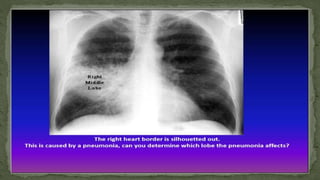

B. Lung consolidation

C. Pneumonia

 The opacification is caused by fluid or solid material within the

airways that causes a difference in the relative attenuation of the

lung:

 Transudate, e.g. pulmonary edema secondary to heart

failure

 Pus, e.g. bacterial pneumonia

 Blood, e.g. pulmonary hemorrhage

 Cells, e.g. bronchoalveolar carcinoma

 Protein, e.g. alveolar proteinosis

 Gastric contents, e.g. aspiration pneumonia. water, e.g.

drowning